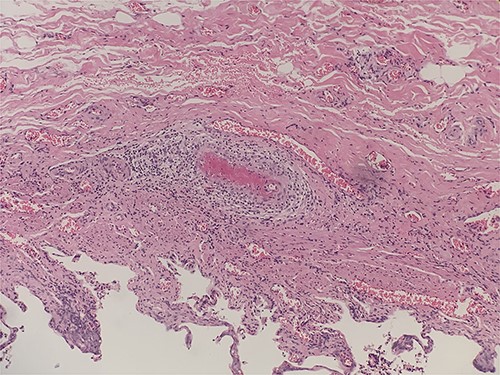

He underwent laparoscopic cholecystectomy under general anesthesia in the standard way. The gallbladder was found to be macroscopically inflamed with few omental adhesions. The procedure was completed peacefully, and the patient recovered well. The histology of the gallbladder specimen came back showing features of necrotizing vasculitis of small and medium arteries suggestive of PAN (Figs 1–3). He was treated with steroids for his systemic vasculitis and has shown significant improvement in his symptoms. His kidney function also markedly improved.

Intraluminal thrombi, fibrinoid necrosis with perivascular infiltration by lymphocytes, neutrophils, and eosinophils (H&E 200X).